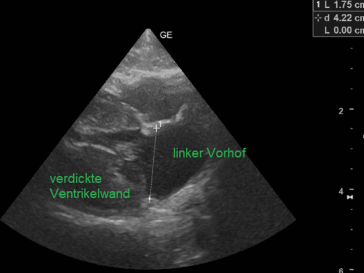

Mit dem Ultraschall werden der Herzmuskel und seine Anhänge dargestellt. Die verdickten Klappenteile, das Ausmass des Pendelblutes, der vergrösserte Vorhof und Ventrikel sowie die Druckdifferenzen sind mess- und darstellbar. Nach dieser systematischen Erfassung und Beschreibung beurteilt die Tierärztin den Schweregrad der Erkrankung und definiert Therapie-Optionen.

verdickte Ventrikelwand mit vergrössertem linkem Vorhof

Gewöhnlich zeigen sich klinische Symptome bei der mittelalten Katze, aber auch Jungtiere oder bereits alte Katzen können Probleme zeigen. Wenn sich der Herzmuskel nur fokal, segmental und geringgradig verdickt, zeigen sich bestenfalls keine Symptome. Ist die Verdickung des Herzmuskels aber hochgradig und global, dann kann er seine Funktion nicht mehr wahrnehmen.

Mit dem Elektrokardiogramm können Arrhythmien aufgedeckt werde. Im Thorax Röntgen erkennen wir eine vergrösserte Herz-Silhouette oder auch einen Flüssigkeits-Rückstau im Lungengewebe oder im Brustraum. Mit der Ultraschalluntersuchung werden anatomische Veränderungen am Herzmuskel-, Flussmuster und Drücke messbar.